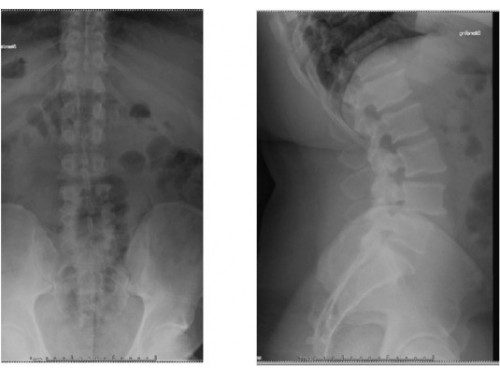

臺北市立聯合醫院中興院區骨科主治醫師劉彥麟曾經遇過一位眉頭深鎖的病患,一跛一跛的走進診間,苦惱的說:「醫生,我沒辦法好好走路已經有一段時間了,雙腳站一下就很痠痛麻木不舒服,諮詢過很多醫院都建議開刀,不知道你的意見如何?」從當時病患的X光影像可以看出來,第三腰椎至第五腰椎滑脫,且外院的核磁共振影像也顯示有嚴重的椎管狹窄,病人表示已接受過藥物保守治療以及復健,但效果不明顯。在與病人多次溝通並詳細解釋開刀風險及日後恢復情況後,病患決定開刀治療,手術解決了病患雙腳麻木痠痛的問題,也改善行走情況,回家上下樓梯已經不再是很痛苦的事情,甚至站立超過三十分鐘以上都沒有問題,生活上得到很大改善,最重要是終於看到他的笑容。

劉彥麟進一步說明,該名病患因為脊椎不穩定而且神經壓迫嚴重,因此選擇椎弓鋼釘置入、完整減壓及脊椎內支架來達到穩定脊椎及神經放鬆的效果,術後第三天即可下床走路,一個禮拜後回家休養,叮嚀照顧好傷口及穿戴護腰保護開刀處,適當的休息,幾個月後成功擺脫神經壓迫造成的麻木痠痛,獲得一個新的人生。